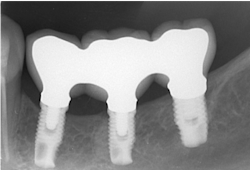

The same arguments have been advanced for not splinting adjacent implants in segmental reconstructions (figure 1). Plaque-related peri-implantitis is the most common biological complication in implant dentistry. A passive fit of prostheses on their supporting implants is considered essential for minimizing mechanical and biological overloading. On the other hand, it is also claimed that splinting can prevent overloading (figure 2). Screw loosening and fracture of veneering material are the most common mechanical complications of loading, although there is little evidence that it results in loss of integration.

Figure 2: Splinted adjacent implants